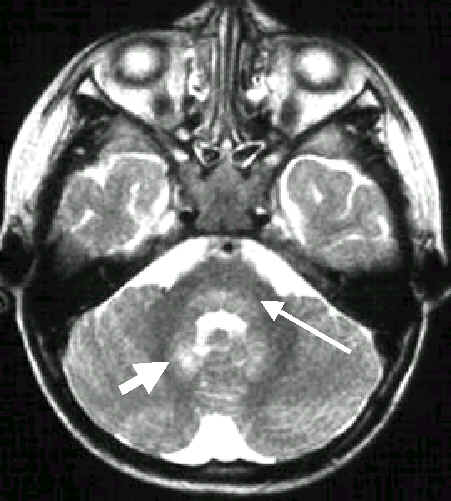

這一波肆虐台灣的腸病毒,據估計,全省大約有十萬名兒童受感染,以手足口

症及咽峽炎為主要症狀,但有少數(至7月10日止共271人),嚴重到住入全國

各大醫院的小兒加護病房,並且有54名幼童因此失去寶貴的生命,所以粗略估

計重症者在千分之2.7左右,死亡率在萬分之五左右。這些重症者臨床表現出

昏睡、心跳加快、呼吸急促、血壓下降,嚴重者會休克、死亡等。目前大家都

已同意這些重症者,主要是因為病毒侵犯腦幹所引起的,並已獲得數例屍體解

剖証實,以及中國附設醫院和彰基的磁振造影做佐証。

在這波腸病毒流行中,除了手足口症、咽峽炎和腦幹腦炎之外,有小部份的幼

兒也表現出小兒麻痺似症狀(polio-like syndrome),而且以單肢麻痺(monoplegia)

,即單側上肢或單側下肢麻痺為主要表徵。

中國醫藥學院附設醫院在這波腸病毒流行中,迄今70例有中樞神經感染的患者

中,3例出現單肢麻痺,其中2例是上肢麻痺,1例是下肢麻痺。下肢麻痺這例

是14個月大男孩,先有手足口症,5天後又因心跳加快、呼吸急促而住入加護

病房,當時磁振造影已証實他的腦幹受侵犯,小兒科醫師予以成功治療脫離危

險之後,又發現他的左下肢麻痺,磁振造影檢查發現胸椎脊髓末端脊髓灰質左

側有病變,表示受病毒侵犯(見附圖),與臨床症狀相吻合。事實上這個受侵犯

的位置正是一般小兒麻痺者脊髓被侵犯的位置,只是他被侵犯的是脊髓的一側

,因此只引起單肢麻痺。這個小男孩如我們所預料的每天都在明顯地進步中,

並已出院,他的單肢麻痺應可在一個月左右完全復原。